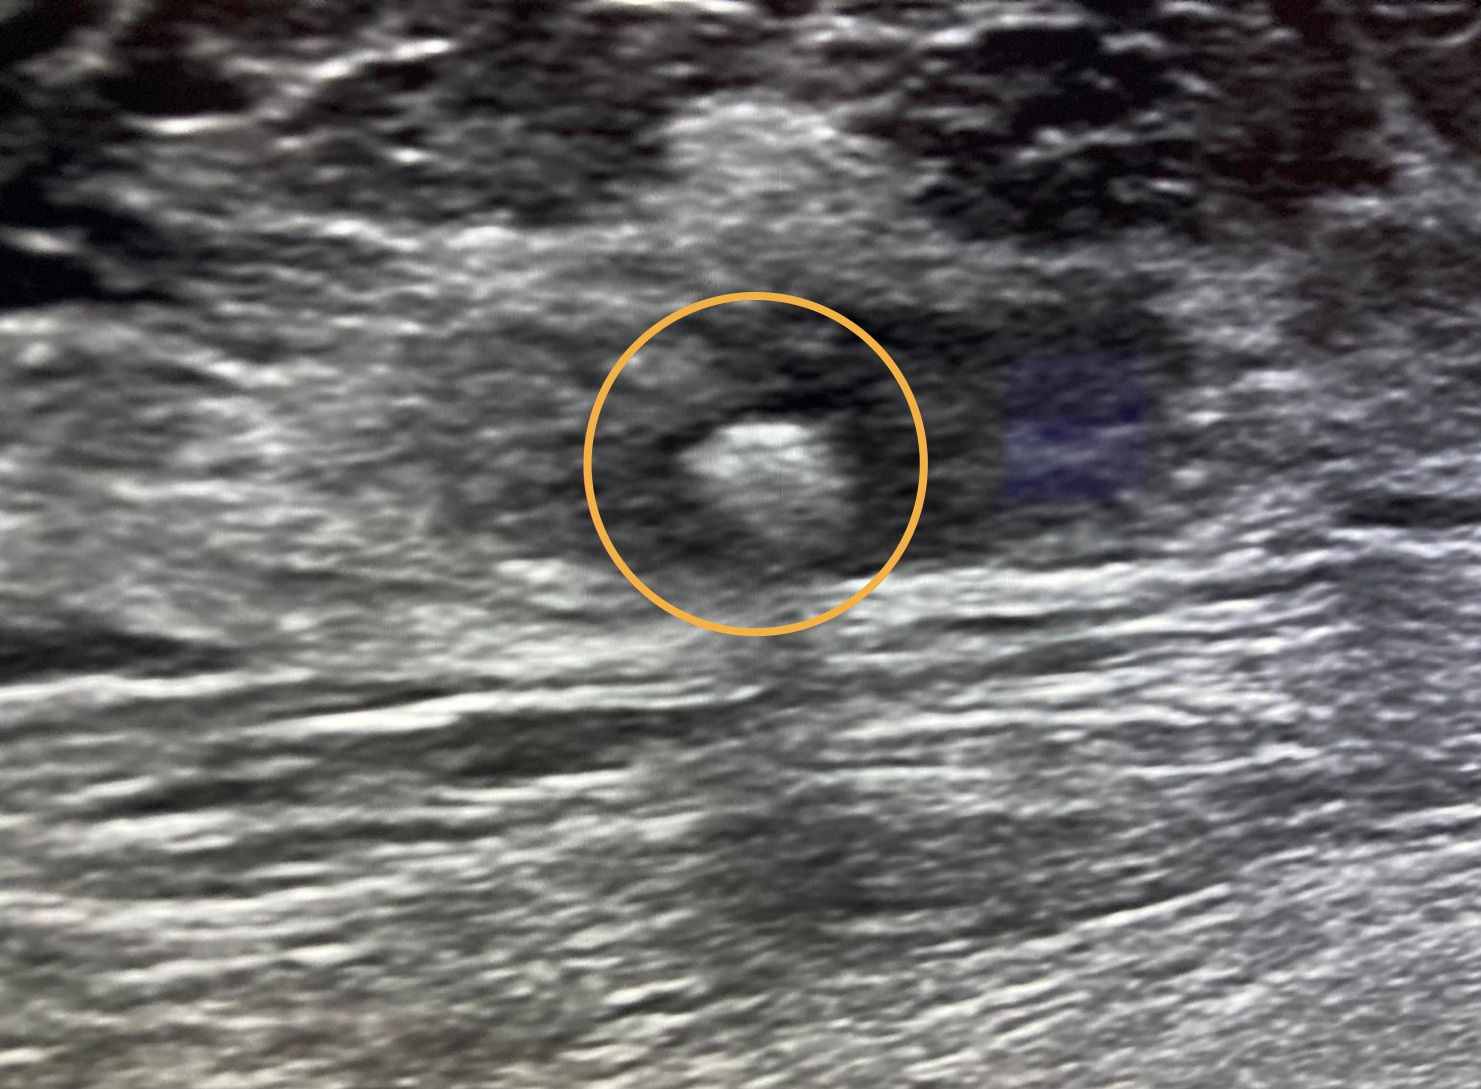

Ultrasound image showing Gold Anchor implanted in breast to mark a biopsy site.

- The Gold Anchor markers are pre-loaded in industry leading thin 20G needles.

- When deployed, Gold Anchor expands outside the needle and attaches immediately into the tissue.

- Gold Anchor can be implanted percutaneously, guided by stereotactic mammography, ultrasound or CT.